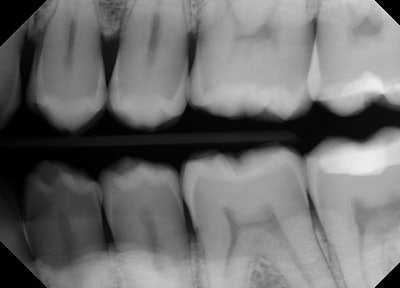

A patient presented for class II restorations due to primary decay on the interproximal surfaces of teeth #12 and #13 (Figure 1 and 2). Clinically the tooth was cold-tested and confirmed a normal response to cold stimulus.

Figure 1: Preoperative bitewing showing primary decay on the distal of tooth #12 and the mesial of #13. Images and captions courtesy of Dr. Ben Alvarez.